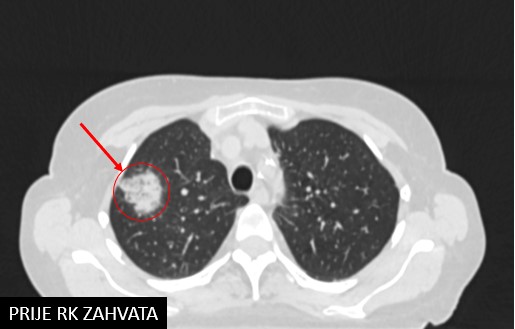

Adenoca mucinosum lobi sup pulm dex (2019.)

SABR pulmonis dex (13.3.2019.)

SABR pulmonis dex (9.4.2022.)

Rezultat – 55 mjeseci nakon RK

Potpuni nestanak tretirane lezije